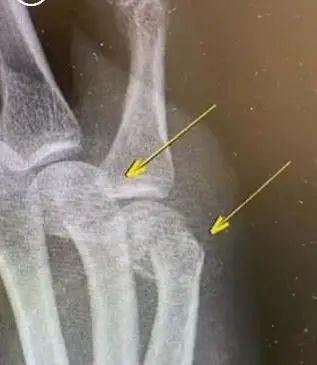

右手第四第五掌骨肿胀明显

最后只能住院做手术

在手掌里打了钢板